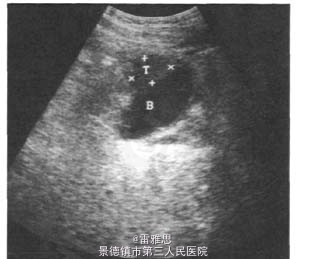

3、查体:未见明显阳性体征 4、辅助检查:泌尿系B超示:膀胱占位。盆腔CT示:膀胱右前壁增厚,考虑占位。胸片及肝、胆、胰、脾B超未见异常。胃镜及肠镜未见占位。膀胱镜检:膀胱右前壁见絮状新生物。膀胱镜病理诊断:印戒细胞癌。